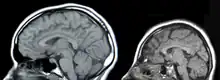

| A baby with microcephaly (left) compared to a baby with a typical head size | |